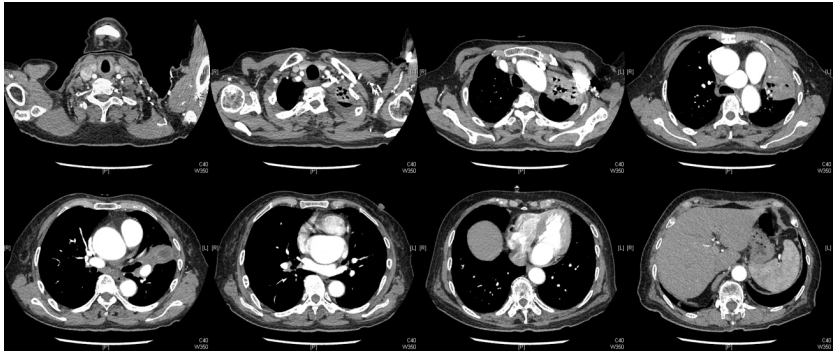

由于厌氧菌培养非常困难,既往我们对厌氧菌的认知仅限于在消化道定植,对其致病机制以及何种情况下致病并不非常清楚。厌氧菌定植于皮肤黏膜,是一种内源性微生物,感染发生率高,可导致严重、致死性感染。由于标本采集和转运的特殊性,使厌氧菌难以分离;加之其培养困难,体外生长慢,所以既往很难识别。厌氧菌在治疗方面存在一定挑战,如往往混合多重感染,且易产生耐药,也会因治疗延迟导致治疗失败。随着近10年来NGS技术的应用和普及,我们对厌氧菌的认识得以提升。常见的致病厌氧菌分为革兰阳性球菌、革兰阴性球菌、革兰阳性非芽孢杆菌、革兰阳性芽孢杆菌以及革兰阴性杆菌(表1)。革兰阳性非芽孢杆菌中可能致病的是放线菌,例如龋齿放线菌参与龋齿的发病过程。革兰阳性芽孢杆菌往往具有致病性,其中产气荚膜杆菌、艰难梭菌/难辨梭状芽孢杆菌、肉毒杆菌/肉毒梭菌、破伤风梭菌/杆菌具有强致病性。革兰阴性杆菌中的拟杆菌属对青霉素类药物具有很强的耐药性,易致青霉素治疗失败。临床中我们与厌氧菌的接触逐渐增多,对其特点也会愈发熟悉,对于临床诊断和治疗也会有所帮助。在NGS报告中通常会将检出的厌氧菌列为“C类”,定义为致病性C类—呼吸道正常微生态菌群,一般不导致感染。但当患者存在误吸风险时,需关注厌氧菌引起肺脓肿的可能。此时就需要针对患者的危险因素、临床表现、影像学、病原学以及气管镜下特点等进行综合分析。微小单胞菌最早是通过培养进行鉴定。瑞士2015—2022年132例病例报告的培养鉴定结果显示,血液中检出微小单胞菌37例(28%),肺内(肺脓肿、脓胸)检出29例(22%),总体病死率较低(5.3%)。国内周华教授团队开展的一项回顾性研究分析了2019年1月至2020年7月经病理活检和mNGS诊断的5例与微小单胞菌相关的慢性肺脓肿患者。患者的平均病程为6.5个月,共同特征是口腔卫生差,有酗酒史,且CT表现为边界不规则的高密度团块状实变影,并且在病灶中间可见液化性坏死,但没有发现气液平面或空腔,所以前期易被误诊为肺癌。下图1是该研究报告中病例3的肺部CT表现。时间点1:首次就诊时,左下叶可见团块状肺不张,伴周围磨玻璃样渗出病变,中心坏死不明显,可见细小空气囊泡影。时间点2:发病8个月时,可见大面积肺实变,增强CT示病灶内有液化坏死和小空洞。时间点3:经过3个月的有效抗厌氧菌治疗,病灶明显缩小,遗留空洞和纤维增殖病灶。图2是病例4的肺部CT表现。时间点1:患者首次就诊时,右上叶可见肿块样肺部实变影。时间点2:发病8个月时增强CT,可见实变明显增大,病灶内出现液化坏死。时间点3:经过3个月的有效治疗,病灶明显缩小,有残留空洞和纤维瘢痕样病变。由于通过影像学鉴别该病与肺癌具有挑战性,所以5例患者都接受了支气管镜检查和CT引导下经皮肺活检。5例患者经组织活检或支气管肺泡灌洗液(BALF)标本mNGS检测到微小单胞菌。病例: 女性, 67岁, 主诉"咳嗽咳痰2个月"。现病史:2个月前,患者家属感染新冠病毒(家属新冠抗原阳性)之后,患者出现咳嗽咳黄脓痰,无痰中带血及痰液拉丝,痰无臭味,无胸闷气短及胸痛,无咽痛咽痒,无鼻塞流涕。6月9日于当地市医院住院,住院期间出现发热,体温最高38.6℃,无寒战,查新冠病毒核酸阳性,予先诺特韦/利托那韦片口服治疗。查胸部CT见左肺上叶软组织影,左肺上叶炎症。诊断肺脓肿,予头孢唑肟联合莫西沙星,治疗后复查胸部CT(6月26日)病灶较6月9日明显吸收好转。6月14日气管镜检査见左肺上叶支气管开口狭窄,见大量脓性痰液堵塞支气管开口(病原学结果家属无法提供)。6月30日办理出院后仍有咳黄脓痰,无发热畏寒,口服止咳化痰药物,未使用抗生素。7月30日复诊胸部CT见左肺上叶异常密度较前增大。8月2日再次于当地市人民医院住院。8月4日气管镜检查: 左肺上叶黏膜肿胀肥厚, 管腔狭窄, 见大量白色干酪样分泌物涌出, 支气管镜不能进入。内科予莫西沙星静滴治疗10天, 外科予莫西沙星联合哌拉西林他唑巴坦静滴9天。复查胸部CT见病灶较前进展, 且右肺出现新发感染病灶。病程中患者饮食可, 睡眠差, 二便正常, 体重减轻5 kg。既往对阿莫西林过敏, 表现为口服阿莫西林后全身皮疹。否认嗜酒史及吸烟史。入院后胸部增强CT可见病灶内液化坏死,同时伴有小的空气囊泡影(图3)。患者有胸痛症状。气管镜检查发现气道内有痰栓或黏液栓阻塞征象(图4)。灌洗液tNGS结果回示:微小单胞菌(序列数2762),巨细胞病毒(序列数171),副流感病毒(序列数79),EB病毒(序列数61)。考虑病毒不会导致气道内如此改变,但由于微小单胞菌属于常见口腔定植菌,此时也不能完全确定微小单胞菌是否为引起感染的主要责任病原体。8月24日起予莫西沙星0.4 g qd ivgtt+哌拉西林他唑巴坦4.5 g q8h ivgtt。经过上述治疗,患者局部病灶有所吸收,但整个肺叶并无明显改善(图5)。气管镜检查仍然发现气道内有较黏稠的黏液栓阻塞气道开口(图6)。治疗经过:气管镜下予以局部冲洗,再次送检tNGS。9月7日结果回示:微小单胞菌(序列数6464),较前明显增多;副流感病毒(序列数998),EB病毒(序列数331)。9月9日起调整治疗方案为美罗培南1 g q8h。9月12日复查患者胸部CT,可见肺通气部分改善,肺组织内实变较前吸收(图7)。第三次气管镜检查仍可见少量痰栓嵌塞在远端支气管开口(图8)。患者此后转入医联体医院继续抗感染治疗。病例2:女性,54岁。主诉:咳嗽咳痰2个月,发热1周。现病史:入院2个月前,患者在西南地区旅游时感冒,出现咳嗽咳痰,白痰为主,量多,无胸痛,无发热,无痰中带血,咳时气短。于河北某诊所间断输液治疗14天(具体不详),期间口服中药治疗,症状未缓解。入院3周前(2023-09-07)就诊于当地县医院,查胸部CT提示右肺炎症,静脉滴注氨曲南、左氧氟沙星、氨溴索治疗1周,症状未缓解。2023年9月14日复查胸部CT显示右肺炎症较前加重,于当地中心医院住院。动脉血气分析:pH 7.43,PaCO2 38.4 mmHg,PaO2 67 mmHg,SaO2 94.2%;血沉90 mm/h;生化:白蛋白35.3 g/L;CRP 82.7 mg/L;血常规:WBC 9.75×109/L,NEU 6.83×109/L,HGB 104 g/L。静脉滴注莫西沙星。入院10天前,行肺穿刺活检,病理回报为少量肺组织及纤维结缔组织,炭末沉积,较多中性白粒细胞、淋巴细胞及浆细胞浸润,伴脓肿形成;肺穿刺mNGS结果回报:微小单孢菌(序列数2650),鲍曼不动杆菌(序列数17),人类疱疹病毒4型(序列数60),人类疱疹病毒7型(序列数5),文氏密螺旋体(序列数4337),解卵磷脂密螺旋体(序列数1121),齿垢密螺旋体(序列数698)。调整抗生素为头孢哌酮舒巴坦2 g q12h。入院1周前,出现发热,体温最高38.5℃,不伴寒战,咳嗽咳痰无加重,无咯血;复查血常规、PCT、CRP均明显增高(未见报告单);复查胸部X线提示右肺炎症范围增大,右侧胸腔积液。更换抗生素为哌拉西林他唑巴坦4.5 g q8h。4天前,支气管镜下见右肺下叶背段支气管略狭窄,黏膜水肿,可见脓性分泌物溢出。BALF革兰染色查见革兰阴性杆菌,抗酸染色、霉菌未见异常,培养未回报。患者体温逐渐降至正常,咳嗽咳痰有所减轻,复查胸部CT提示右肺高密度影,右侧胸腔积液较前增多。为求进一步诊治来我院就诊被收入院。既往甲状腺功能减退病史5年,目前口服优甲乐治疗,监测甲状腺功能指标在正常范围。20年前因宫外孕行手术治疗。2023年10月8日胸部CT示胸膜下斑片状坏死,纵隔窗可见微小空气囊泡影及密度不均匀液化坏死(图9)。治疗:9月28日至10月13日莫西沙星0.4 g qd ivgtt+哌拉西林他唑巴坦钠4.5 g q8h ivgtt。最终患者病灶吸收好转并顺利出院。患者男性,42岁。主因间断咳嗽、咳痰1月余,左侧胸痛、气短2天入院。现病史:入院前1月余(2022-07-19),患者无明显诱因出现咳嗽,咳白痰,痰中有少量鲜红色血丝,左侧胸痛(为钝痛),深吸气后加重,就诊于当地医院。完善肺动脉CTPA:示左上肺动脉舌段分支局部管腔可见线条样低密度充盈缺损,考虑肺栓塞;左肺上叶实性病变伴不均匀强化,性质待定,部分为肺梗死改变可能,纵隔多发稍大淋巴结,性质待定;右肺下叶后基底段可见一不规则实性结节,边缘可见多发毛刺,直径约0.7 cm。当地医院考虑肺栓塞不除外,肺部感染?右肺下叶结节,予莫西沙星抗感染,低分子肝素抗凝,乙酰半胱氨酸化痰。完善CT引导下肺穿刺活检,病理示:肺泡腔扩张伴上皮轻度增生,肺泡间隔纤维组织增生伴散在炎细胞浸润,未见恶性病变。院外规律应用甲磺酸艾多沙班60 mg bid抗凝,先后间断应用左氧氟沙星0.5 g qd、头孢类抗生素(具体药物、剂量不详)抗感染。患者仍有间渐咳黄白痰,量不多,痰中有少量鲜红色血丝;无畏寒、发热、胸痛、夜间阵发性呼吸困难症状,无尿少、双下肢水肿,无口干、咽干,无牙齿成片脱落,无晨僵、关节肿痛,周身无皮疹,无盗汗乏力。2天前(2022-09-16)患者无明显诱因再次出现左侧胸痛,疼痛剧烈,深吸气、咳嗽及改变体位时加重,伴气短,就诊于我院急诊。完善肺动脉CTPA:肺动脉主干及其各叶段分支未见明显充盈缺损,左肺上叶舌段团块影,最大截面约7.6 cm×5.3 cm,边界不清,周围可见晕征;增强扫描不均匀强化,邻近胸膜增厚,性质待定,建议穿刺活检;纵隔及左肺门多发淋巴结显影。血细胞分析:WBC 11.09×109/L,NEU% 80.8%,NEU 8.95×109/L;CRP 54 mg/L,PCT 0.07 ng/ml。患者自发病以来,精神状、食欲及睡眠均一般,大小便正常,体重下降5 kg。2022年9月14日外院胸部增强CT:胸膜下楔形的影像学表现可见少量小气泡囊以及液化坏死病灶(图10)。初始考虑肺部肿瘤及肺栓塞。经过初步抗感染及抗凝治疗,患者病情无缓解,2022年9月27日患者突发胸痛,下肺影像加重并且出现脓胸(图11)。行胸腔穿刺并将脓液送检mNGS,结果回报:牙龈卟啉单胞菌(序列数3)。尽管序列数很低,但考虑是脓肿穿刺结果,因此考虑该菌致病可能。抗厌氧菌治疗:9月16-28日莫西沙星0.4 g qd ivgtt,9月23日-10月12日美罗培南1 g q12h ivgtt,9月28日-10月8日万古霉素1 g q12h ivgtt,10月13-18日莫西沙星0.4 g qd ivgtt+甲硝唑0.5 g tid ivgtt。患者肺脓肿的整体治疗时间约为3个月,病灶逐渐吸收,最终形成一些纤维索条影(图12,图13)。1年后复查病灶基本吸收(图14)。图14 1年后复查胸部CT(2023-08-08)微小单胞菌和卟啉单胞菌这两种厌氧菌在临床中需要引起重视,它们容易引起肺脓肿/脓胸。2024年国内学者Li Yao等在Diagn Microbiol Infect Dis 杂志发表了一篇牙髓卟啉单胞菌感染所致肺脓肿的病例报告,文章也提到在胸水或肺组织活检中,通过mNGS同时检出了微小单胞菌和卟啉单胞菌感染引起的肺脓肿。文章还回顾总结了既往发表的厌氧菌感染引起肺脓肿的病例,2010年报道的是1例脑脓肿患者,2019年报道1例脑炎患者,2022年报道1例脓胸伴呼吸衰竭患者。3例患者预后都比较好,可见厌氧菌亦可导致肺外多部位感染。对于厌氧菌所致肺脓肿的诊断及其引起的脓胸,目前的文献报道仍然较少,我们对它们的认知也有限,因此也提醒大家关注相关疾病的诊断和治疗。我们也已将本研究小组8例微小单胞菌所致肺脓肿的系列病例的研究结果发表(Front Cell Infect Microbiol, 2024, 14: 1416884),可供需要的同行参考。对于厌氧菌感染,我们需要提高警惕。厌氧菌往往在口咽部定植,其引起的脓肿/感染往往多为亚急性或慢性起病。患者通常有发热、胸痛症状,脓肿会逐渐进展。由于厌氧菌与人体本身是一种长期共生的关系,人体对厌氧菌的免疫识别可能处于较低的防御反应状态,所以会形成一个亚急性或慢性的发病过程。通常情况下,因厌氧菌的菌群发生了移位,从卫生条件不好的口腔扩展到相对无菌的肺内,同时开始增殖,由此可能导致感染。因此,对于酗酒以及口腔卫生非常差的人群,我们要重视对其风险因素和病史的排查。患者就诊时可能病情并不重,有胸痛或咯血,很容易误诊为肺部肿瘤,往往在这种情况下进行肺穿刺或气管镜检查,mNGS可以发现较大序列数的厌氧菌。但在mNGS检出厌氧菌后的诊断过程中又容易形成误判——究竟是致病菌,还是定植菌?此时结合患者其他病史和影像学特点(有脓肿/痰栓形成,微小空气气囊泡影),可能提示厌氧菌感染。然而,厌氧菌感染在病原学和影像学诊断方面仍然存在诸多困难,极易漏诊和误诊。微小单胞菌感染患者在气管镜下可以看到典型的脓性分泌物嵌塞气道,导致气道阻塞,也会造成远端气道和肺泡引流障碍。所以,及时处理气道内痰栓,改善引流,可能是使患者获得良好预后的关键。厌氧菌肺脓肿的吸收比较缓慢,抗感染的疗程也比较长,需要在后期诊疗过程中密切随访和观察患者对治疗的反应以及耐药等问题,及时调整治疗方案,适当延长疗程。